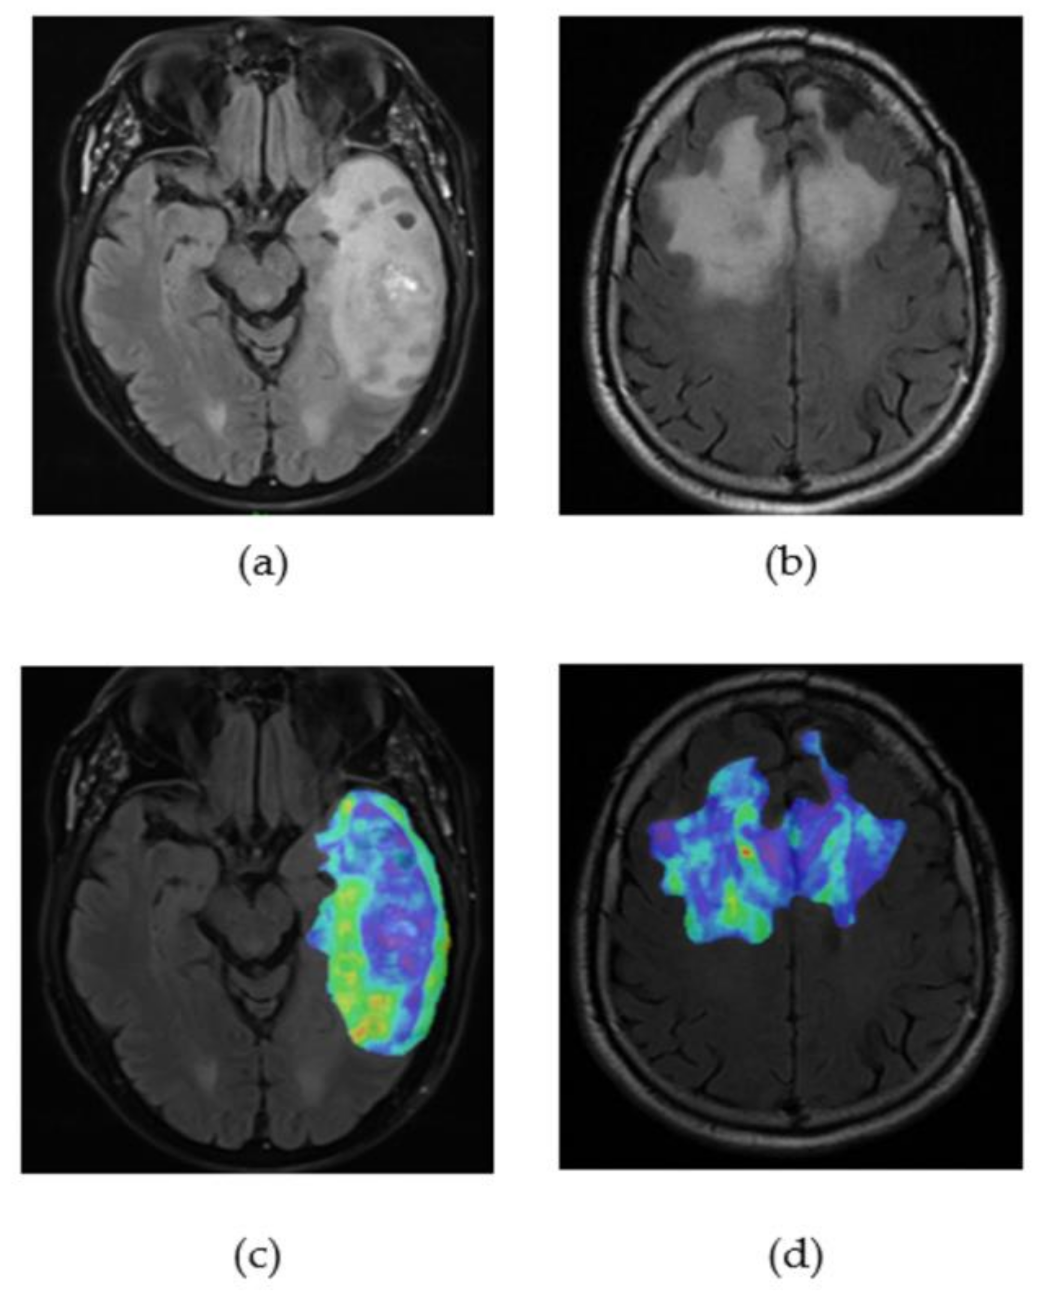

2.3.2. Tumour Segmentation